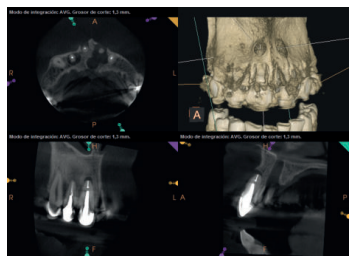

Para confirmar el origen endodóntico y el tamaño de las lesiones se realizaron exploraciones tomográficas con espesor de corte de 75 micras mediante CBCT CS8100 (Carestream Dental® ) en las que se evidenciaron lesiones periapicales radiolúcidas a nivel de 12, 11, 21 (con afectación bicortical), 25 y raíces vestibulares de 26 (Figuras 4 a 8).